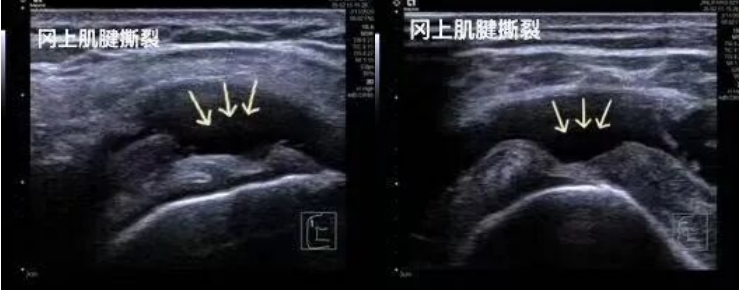

1.運(yùn)動(dòng)損傷:肩袖撕裂、網(wǎng)球肘、跟腱斷裂、肌肉拉傷等。

2.高分辨率與實(shí)時(shí)動(dòng)態(tài)成像:超聲波可捕捉毫米級(jí)的軟組織細(xì)節(jié)(如肌腱纖維的撕裂、滑膜增生),并能實(shí)時(shí)顯示關(guān)節(jié)屈伸、肌肉收縮等動(dòng)態(tài)過程,輔助醫(yī)生精準(zhǔn)評(píng)估功能異常。